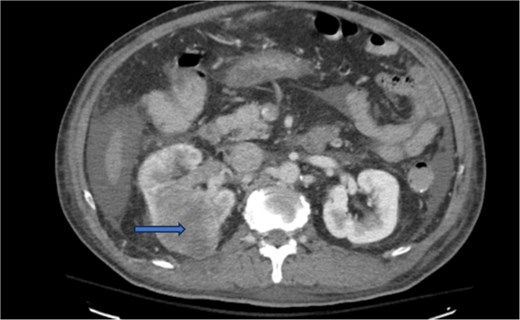

Diagnostic imaging began with a chest X-ray that indicated bilateral pleural effusions. An abdominal ultrasound detected a 4.6 × 4.2 × 4.3 cm echogenic lesion in the right hepatic lobe. Further imaging with a computed tomography (CT) scan of the chest, abdomen, and pelvis revealed a large mass originating from the posterior aspect of the right mid-kidney consistent with RCC (Fig. 1). The mass associated with thrombus extended into the renal sinus and collecting system, traveled along the right renal vein to the inferior vena cava (IVC), and projected into the right atrium (Figs 2 and 3). During hospitalization, bilateral lower extremity pain led to the diagnosis of bilateral deep vein thromboses via duplex venous ultrasound. Echocardiography showed normal left ventricular ejection fraction, impaired diastolic filling, mildly increased ventricular wall thickness, and an echogenic mass extending from the right atrium into the IVC consistent with the tumor thrombus.

CT chest abdomen and pelvis with contrast showing tumor thrombus is seen within the IVC extending over a long distance from the level of the renal vein cephalad into the right atrium.